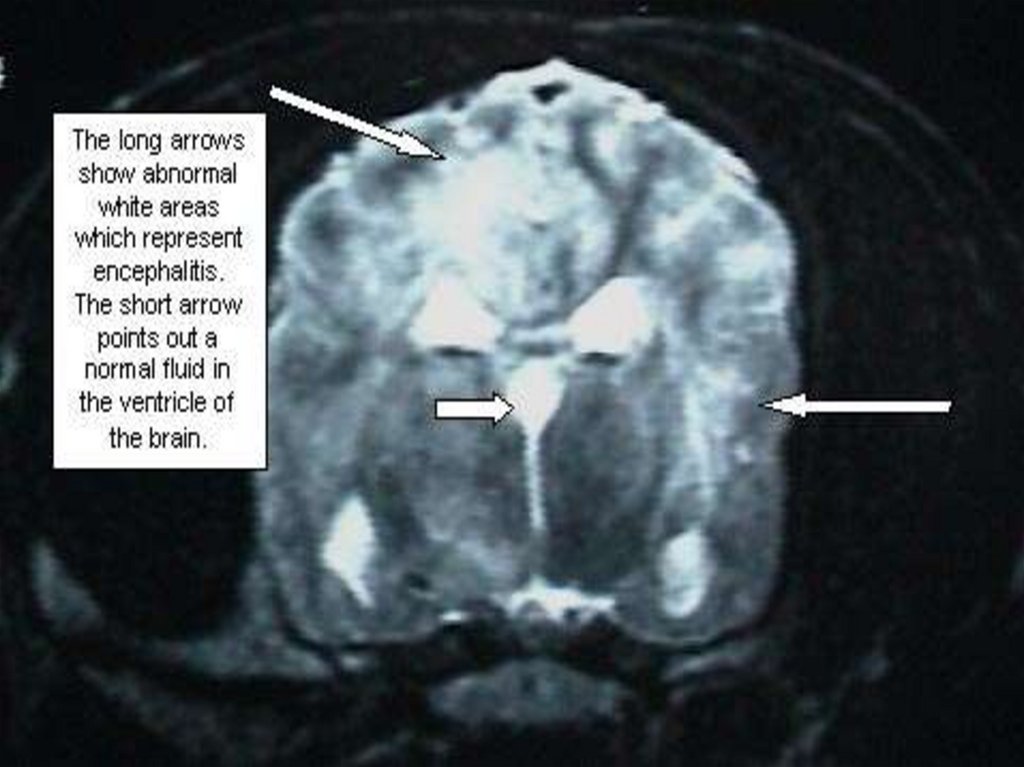

Часто сопровождается синдромом ОТЕКА или

НАБУХАНИЯ головного мозга с такими проявлениями:

- нарушение сознания;

- двигательное беспокойство, судороги;

- расстройство дыхания и деятельности ССС;

- вклинивание продолговатого мозга или

субэпиндимальный отек в области 3 – 4 желудочков

мозга;

- без адекватного лечения – летальный исход!!

МЕНИНГОКОККОВЫЙ МЕНИНГОЭНЦЕФАЛИТ – чаще

проявляется диффузным поражением головного мозга с

потерей сознания и реже отдельными очаговыми

изменениями:

- афазией

3%

- психосенсорные расстройства

1%

- судорогами, моно и гемипарезами

- глазодвигательными расстройствами 27%